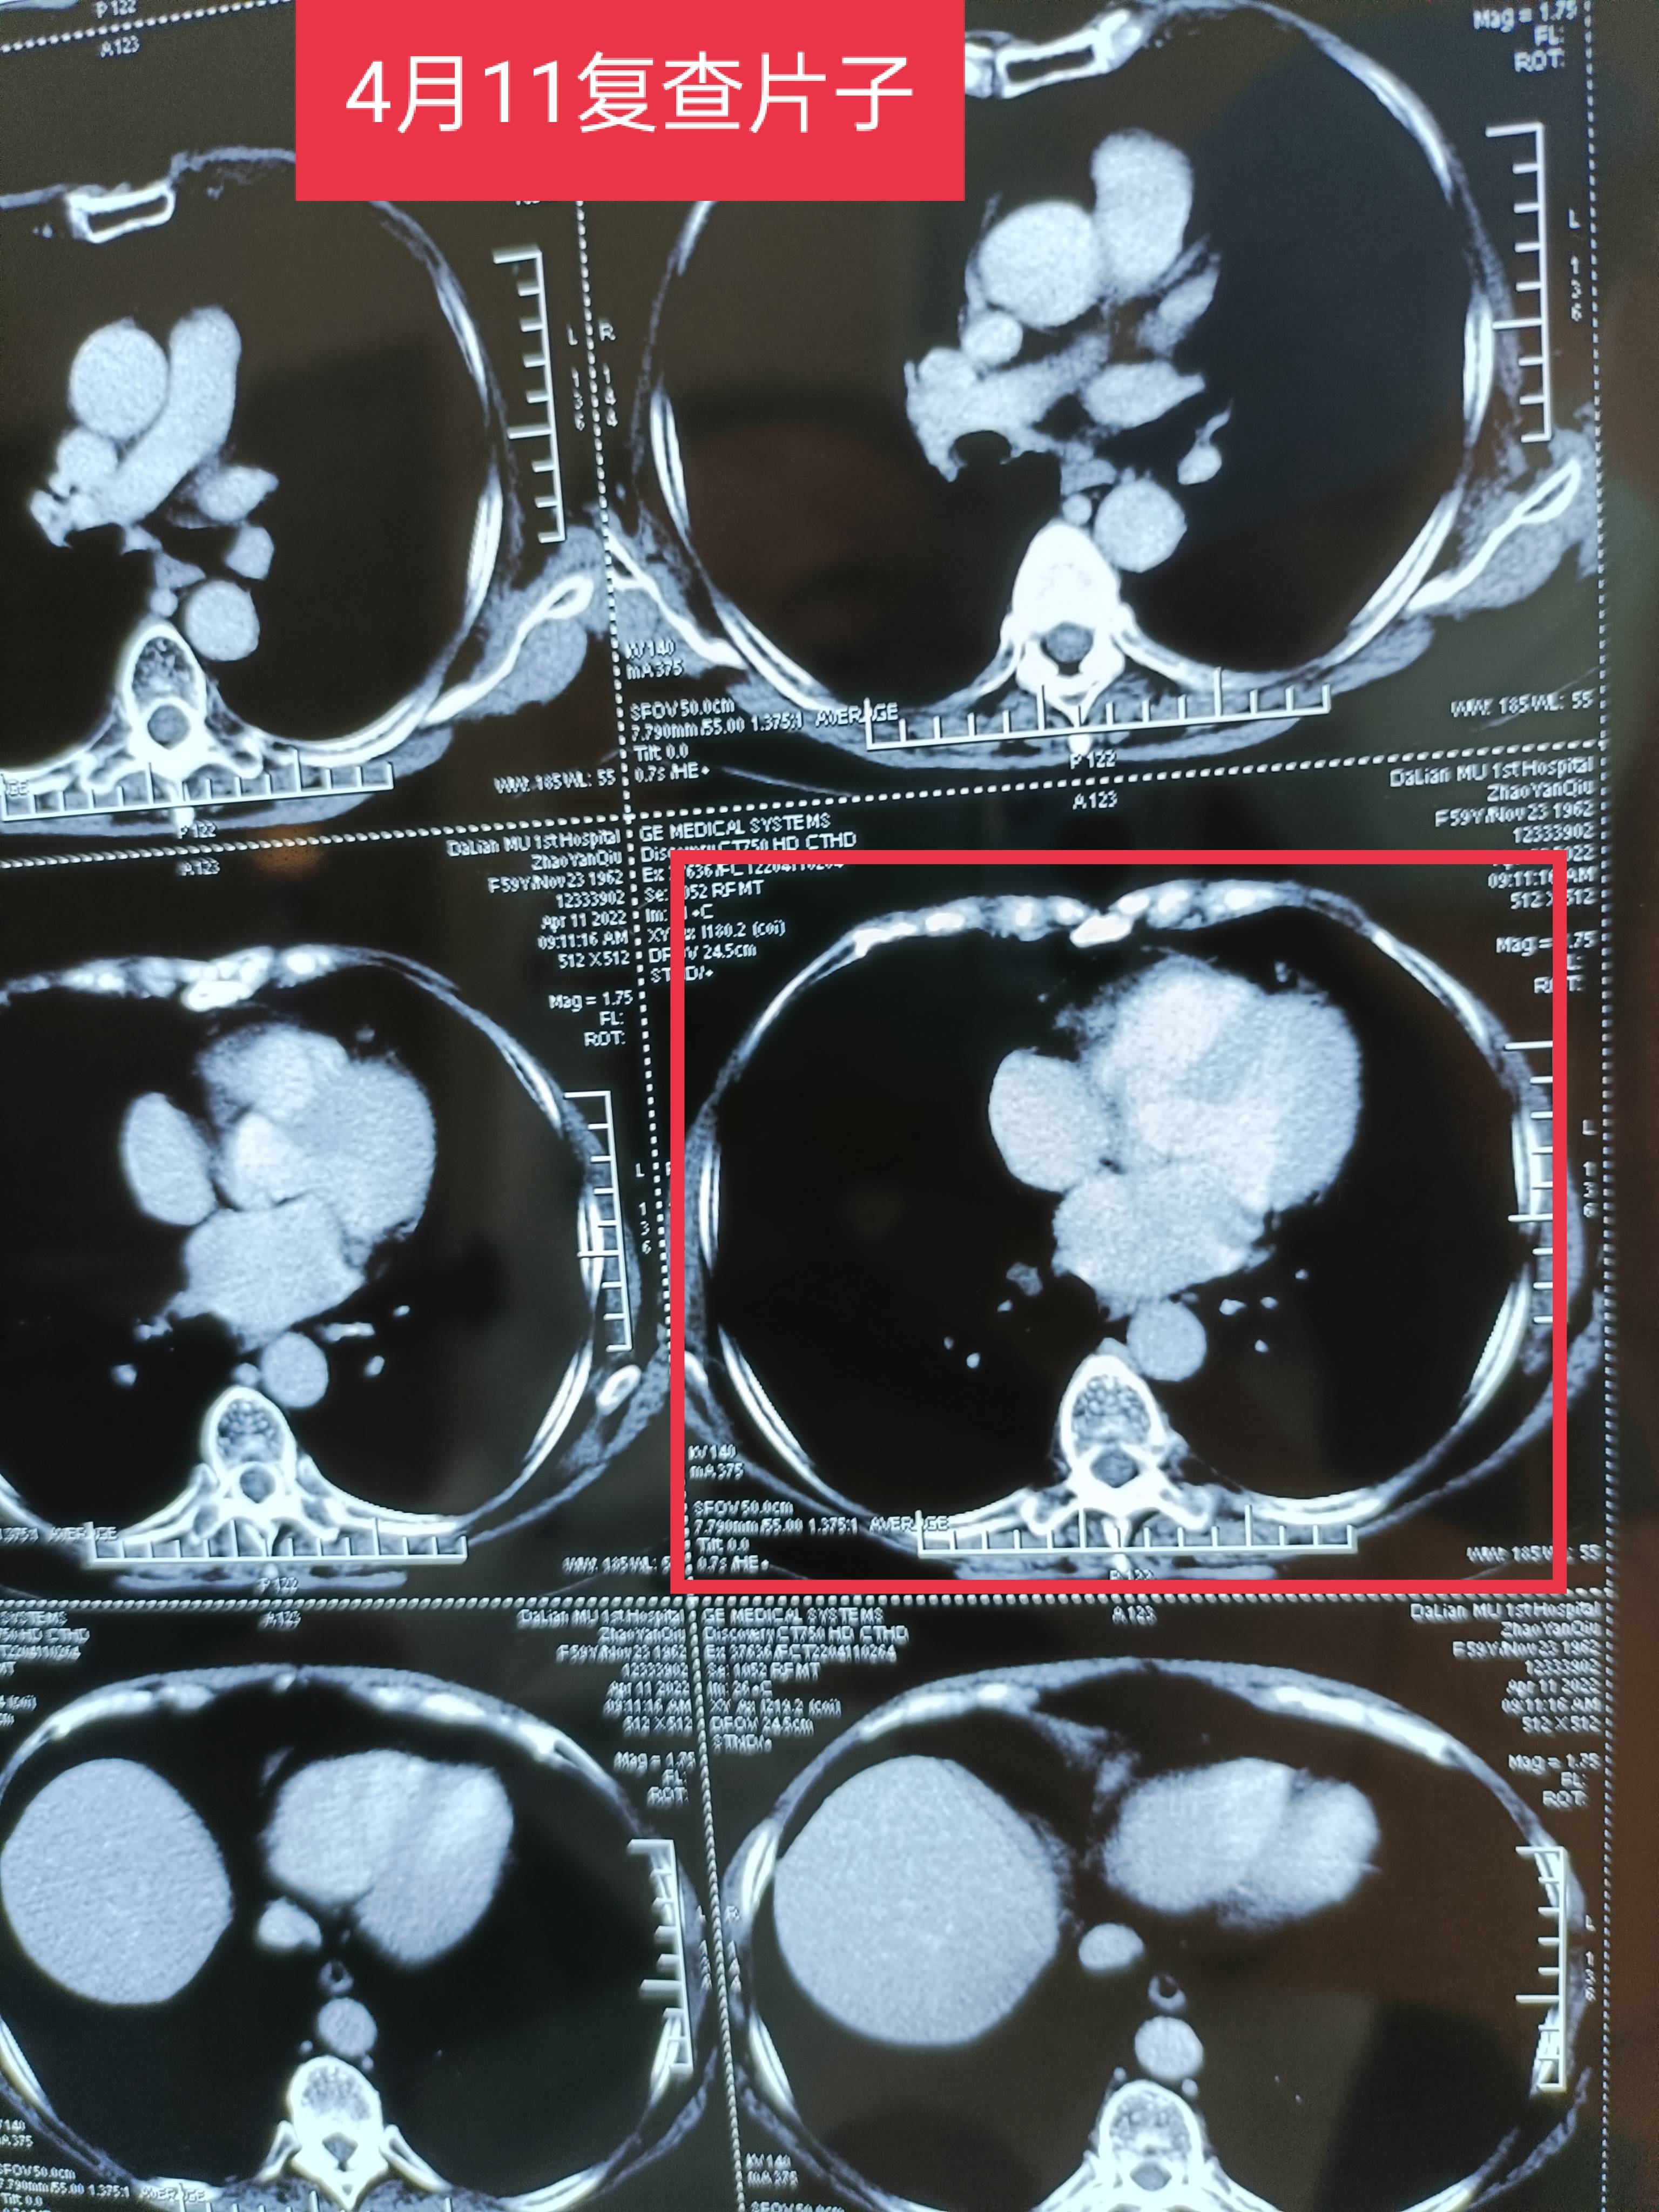

附上确诊到现在不确定复发的片子图,还有从开始到现在的肿标。